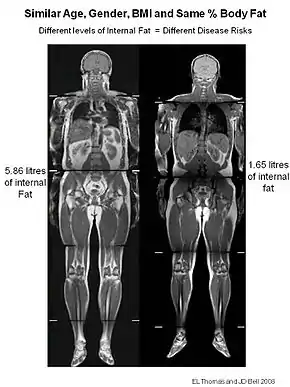

TOFI[1][2] (thin-outside-fat-inside) is used to describe lean individuals with a disproportionate amount of fat (adipose tissue) stored in their abdomen. The figure to illustrate this shows two men, both 35 years old, with a BMI of 25 kg/m2. Despite their similar size, the TOFI had 5.86 litres of internal fat, whilst the healthy control had only 1.65 litres.

To classify an individual as TOFI, it is essential to measure their internal fat content. This is done by using magnetic resonance Imaging (MRI) or CT scanning. The parameters of the MRI scanner are manipulated to show fat as bright (white) and lean tissue as dark.